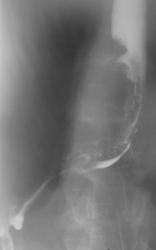

Иллюстрации 2, 3. Складки слизистой оболочки не дифференцируются, рельеф измененной части пищевода характеризуется, как атипический, хаотический. Депо контрастного вещества в виде неправильной формы «ниш», а также точечных «импергнаций» свидетельствуют об изъязвлениях. Стенка пищевода на уровне поражения ригидна. При функциональных дыхательных пробах и при форсированном дыхании, а также при изменении положения пациента пищевод в области пораженной части не смещаем, что косвенным образом свидетельствует «о прорастании», выходе процесса за пределы стенки пищевода.